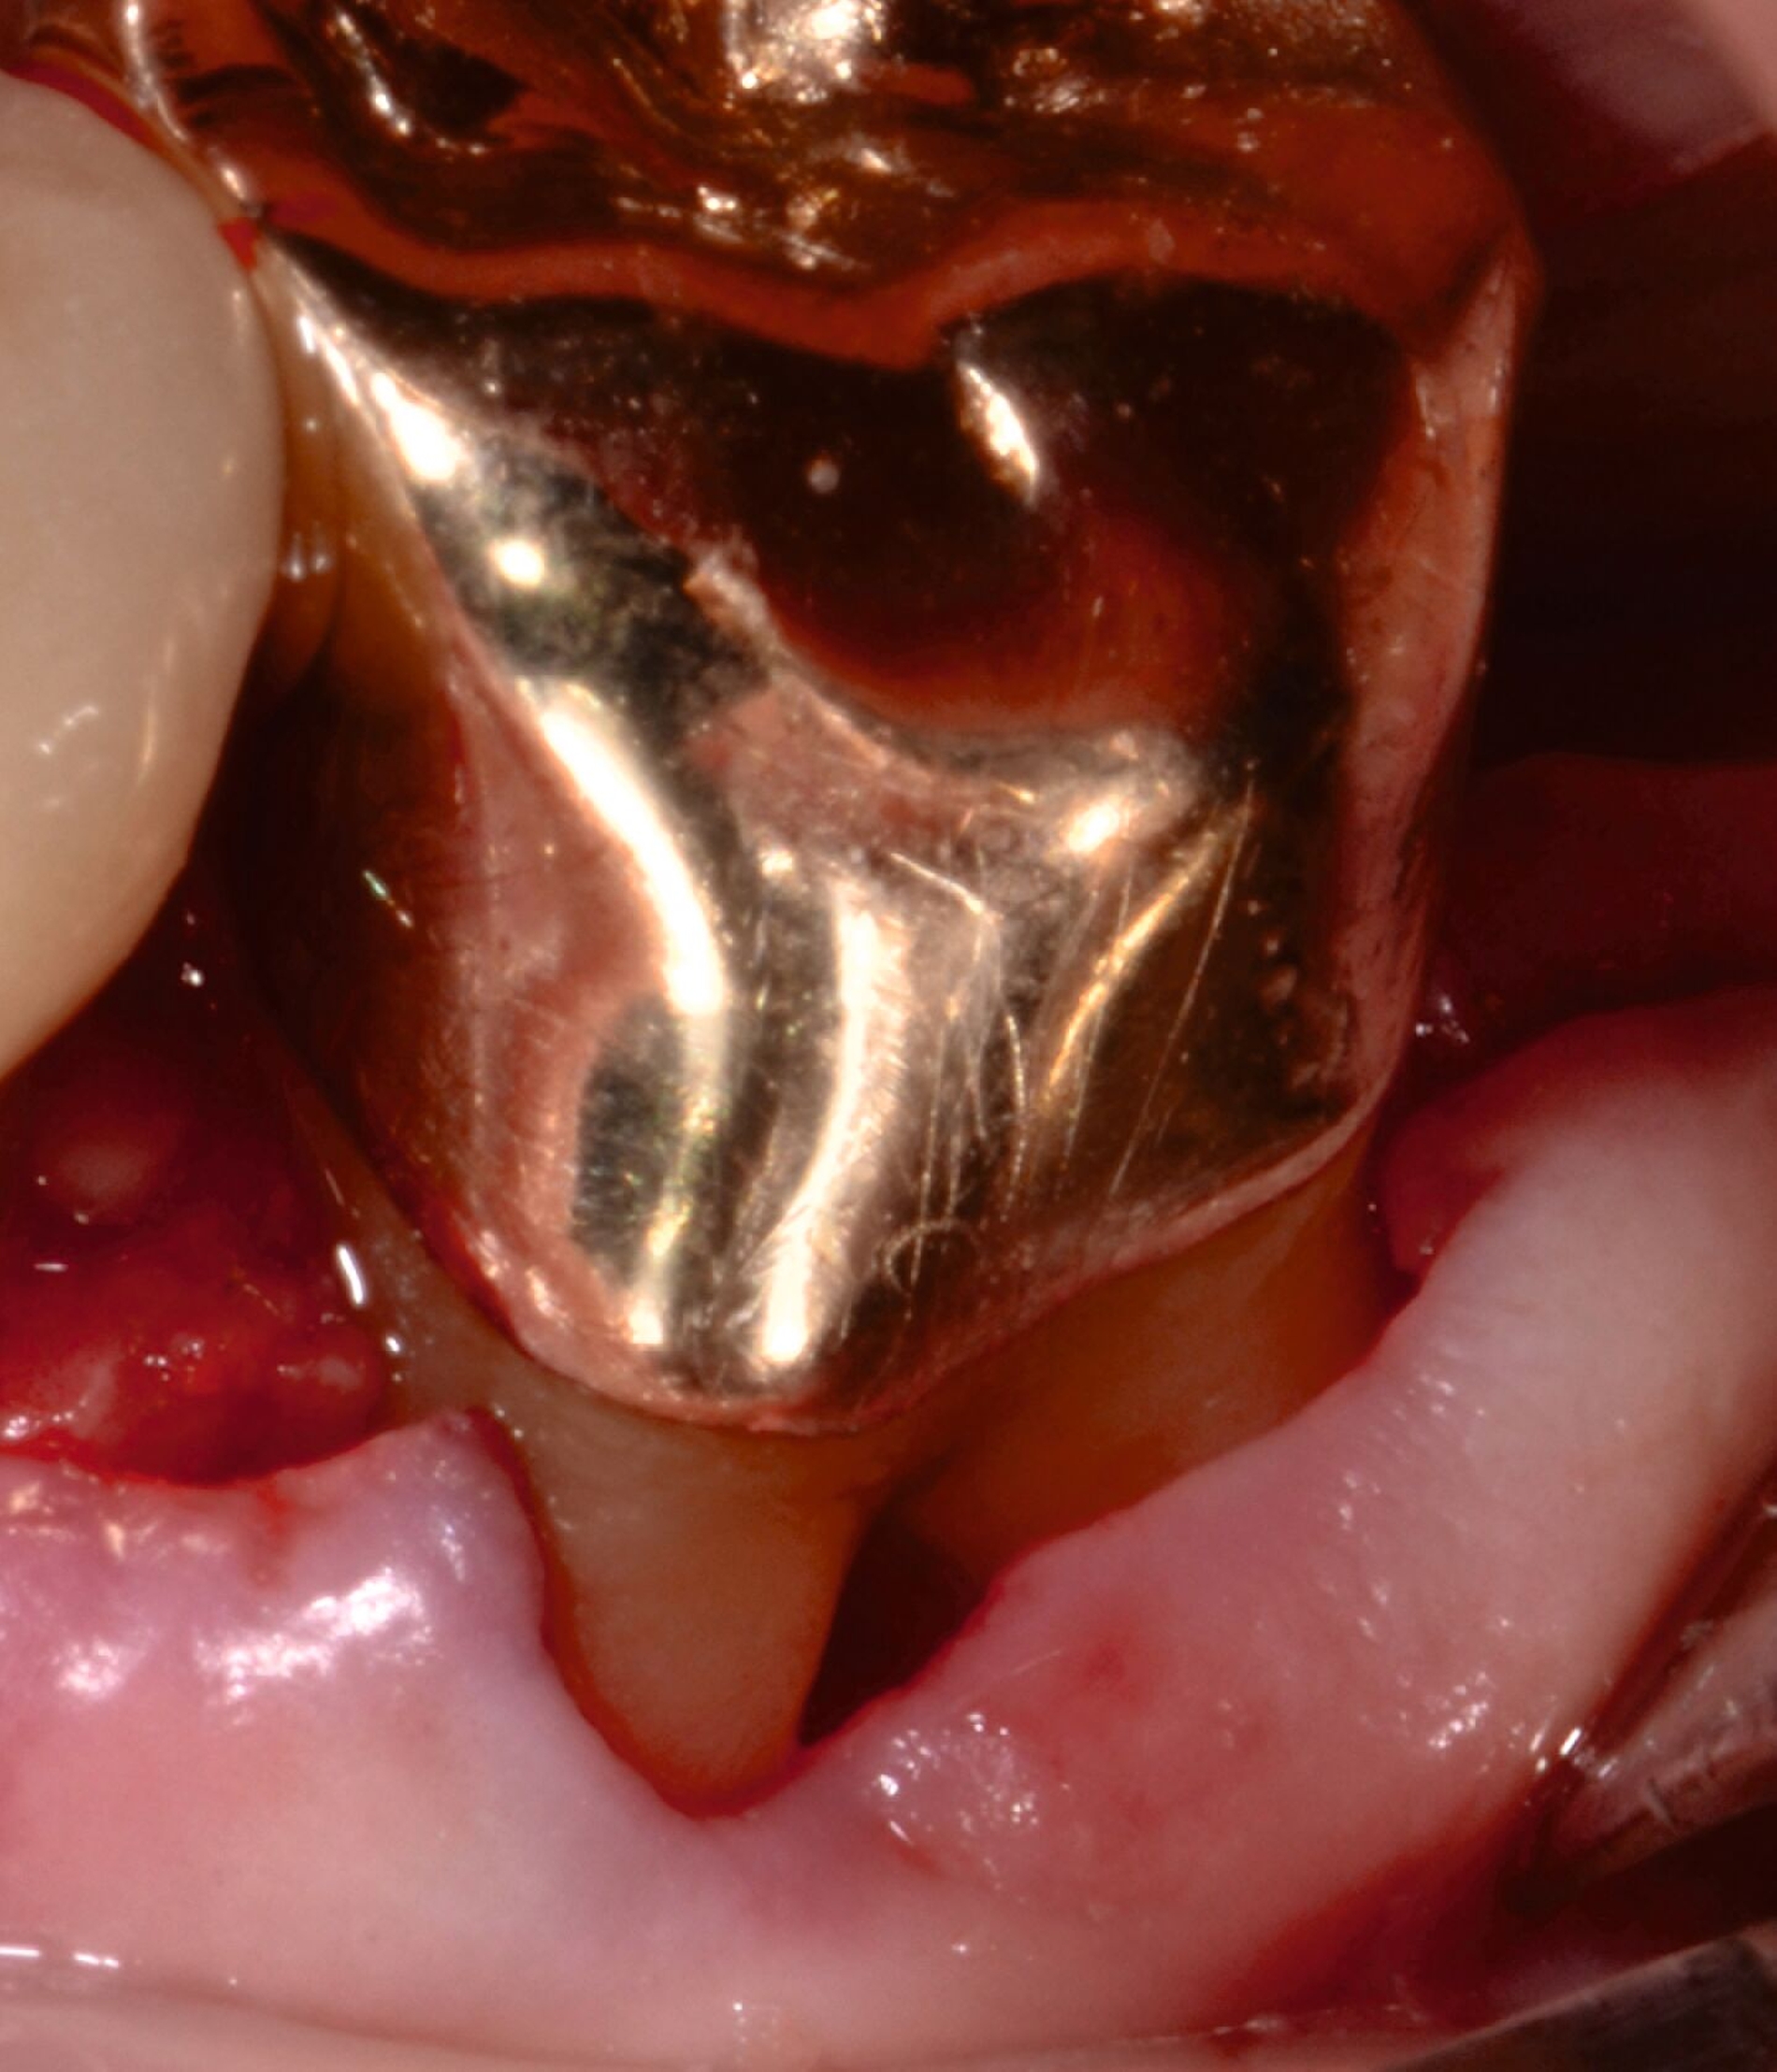

3. Regenerative Parodontalchirurgie

Ziel ist es, einen ausreichenden Zugang zum Defekt für eine sorgfältige Instrumentierung und die Applikation des Biomaterials zu erhalten. Bei isolierten Defekten können vertikale Entlastungsinzisionen verwendet werden. Alternativ kann der Lappen nach lateral zu den benachbarten Zähnen erweitert werden. Keratinisiertes Gewebe sollte durch intrasulkuläre Inzision und die Anhebung eines Mukoperiostlappens erhalten werden. Das Granulationsgewebe wird entfernt und die freiliegenden Wurzeloberflächen werden sorgfältig mit Handinstrumenten, oszillierenden Scalern (optional mit fein diamantierten Spitzen) oder rotierenden Instrumenten gereinigt. Wurzelanomalien wie Schmelzvorsprünge/-perlen sollten entfernt werden. Wenn EMD Teil der Regenerationsstrategie ist, wird es in der Regel nach einer zweiminütigen Wurzelkonditionierung mit Ethylendiamintetraacetat (EDTA) und Spülung mit steriler Kochsalzlösung angewendet. Anschließend kann ein Knochentransplantat/-ersatzmaterial verwendet werden, um den Furkationsdefekt aufzufüllen.